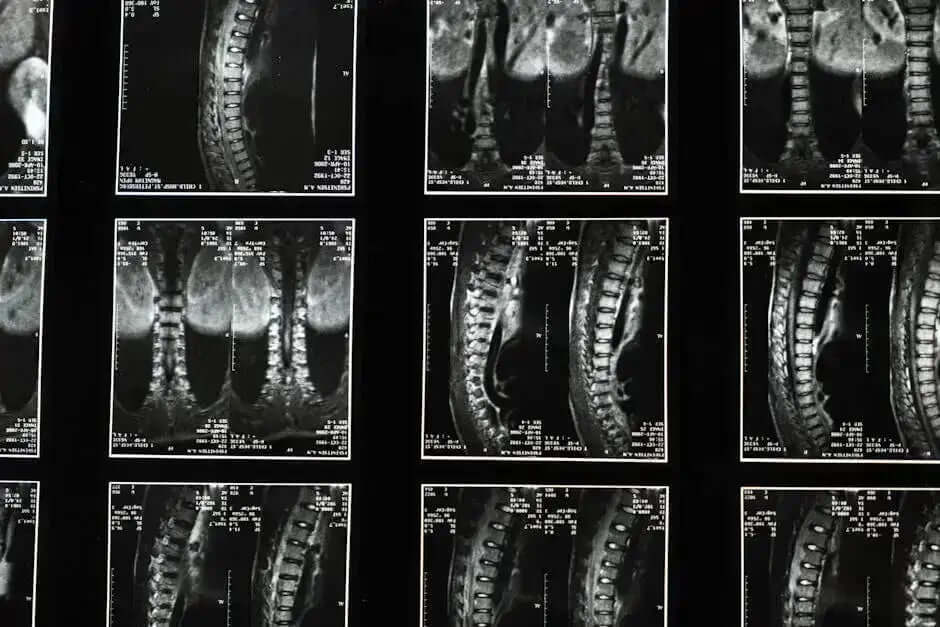

From sore muscles to nerve discomfort, we break down causes

and share expert-backed relief strategies.